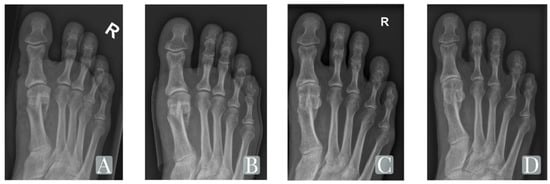

| IM-Angle | 12.6° (±3.2°) | 4.8° (±1.3°) | 5.9° (±1.9°) | <0.001/<0.001 |

| HV-Angle | 24.8° (±4.9°) | 7.2° (±4.4°) | 9.9° (±7.0°) | <0.001/<0.001 |